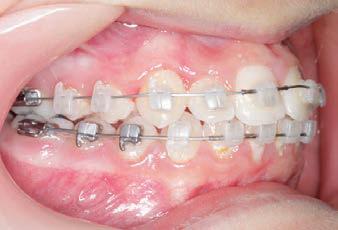

CLASS II DIV.1 - Marra

PROGRESS 1 - 26/9/18 - Class I platform accomplished in 5.75 months with Motion 3D COLOR Appliance

PROGRESS 2 - 26/9/18 - Placement of the SLX 3D Clear Brackets

with M-ONE .015 Cu Nitanium 27°

PROGRESS 3 - 30/10/18 - With M-TWO .020 x .020 Cu Nitanium 35° archwire

PROGRESS 4 - 27/11/18 - 3 links power chain: 5, 4, bypass 3 to crimp hooks

PROGRESS 5 - 13/3/19 - With M-TWO .020 x .020 Cu Nitanium 35° archwire

PROGRESS 6 - 1/8/19 - With M-THREE.019 x .025 Beta Titanium wire